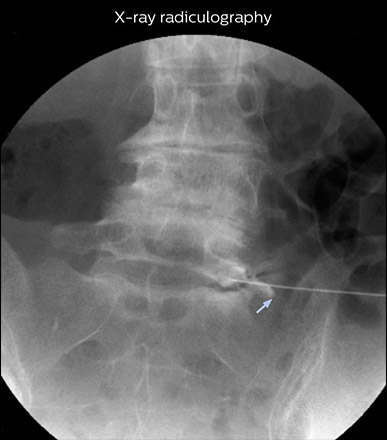

“Before NerveVIEW, diagnosis by MRI alone was sometimes difficult, unless there was a strong suspicion based on clinical symptoms,” says Shoji Yabuki, MD, DMSc, Orthopedic surgeon at Fukushima Medical University School of Medicine. “This is why we routinely perform selective lumbosacral radiculography (nerve root block) and x-ray in such cases. However, radiculography can only depict nerves as far as the contrast agent reaches. When a nerve is distorted by compression, the contrast agent will not pass through this compressed area, preventing us from evaluating the full nerve compression.”

“In such case, we would then browse through axial T2-weighted MR images slice by slice and mentally reconstruct the actual situation based on both radiculography and MRI. Fortunately, NerveVIEW can now very well show nerve courses and presence of nerve compression or edema in one single image series.”

“We have often seen NerveVIEW directly depict details of the nerve compression that were not observed by radiculography. Therefore, we think that with NerveVIEW we can reduce the number of invasive examinations, especially for some patients with lumbar plexus symptoms.”